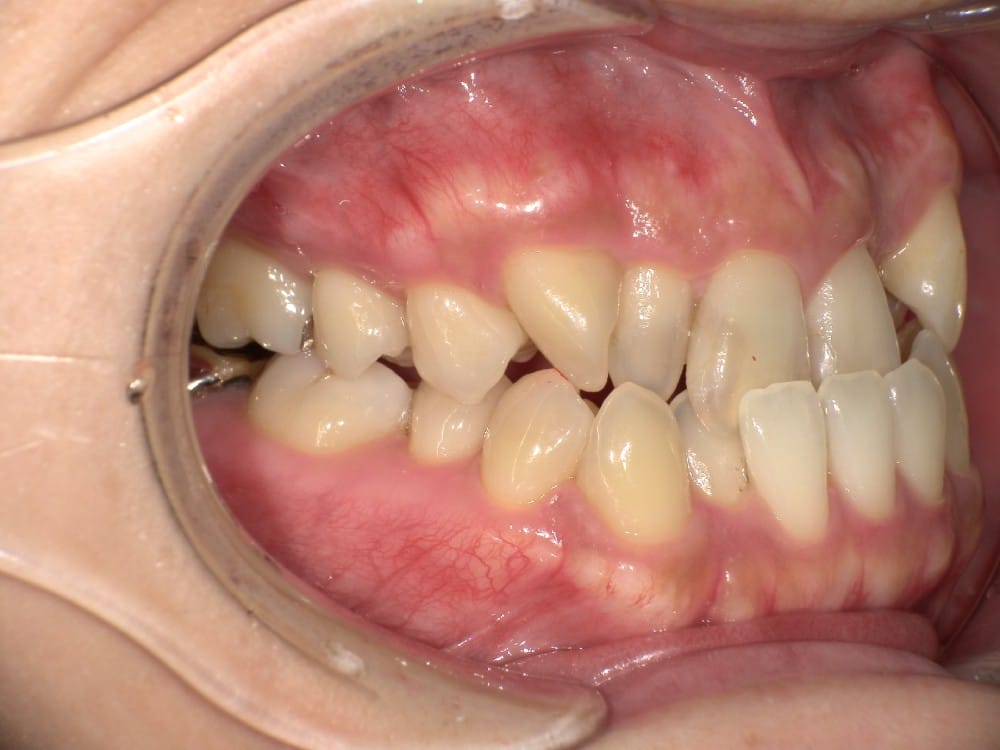

この子は、中学生の女の子で、受け口、横顔が気になるとのことでご来院されました。

治療前の様子

分析をしますと

- 骨格的な上下あごの前後差は中等度

- 噛み合わせの位置も下あごの奥歯が半分くらい前にズレていた

- 上の前歯が前に傾斜、下の前歯が内側に傾斜しているにもかかわらず、受け口

というケースで、外科的な処置も検討するようなケースでした。

患者さまに外科的な手術の選択肢も提示しましたが、希望されず、横顔の変化はおそらく起こらないことを納得の上、治療をスタートいたしました。